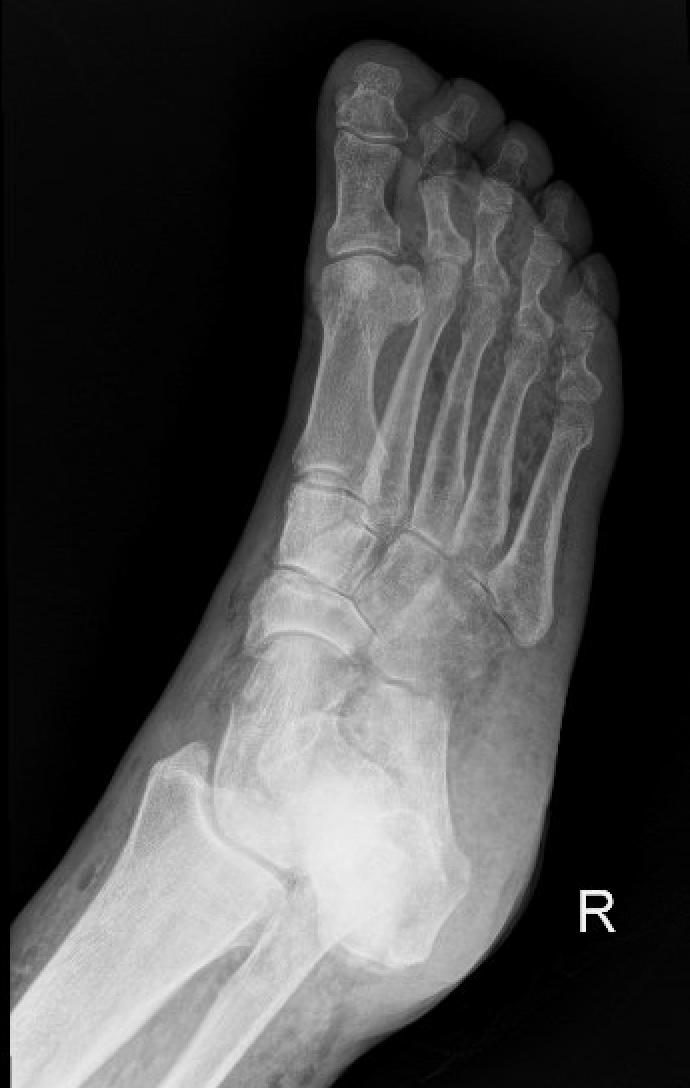

Soft Tissue Case 1

A 50 year old diabetic man presents with worsening pain of a chronic foot wound. He is ill-appearing with a wound on his foot that appears infected. There is palpable crepitus. What is the diagnosis and management based on this XR?